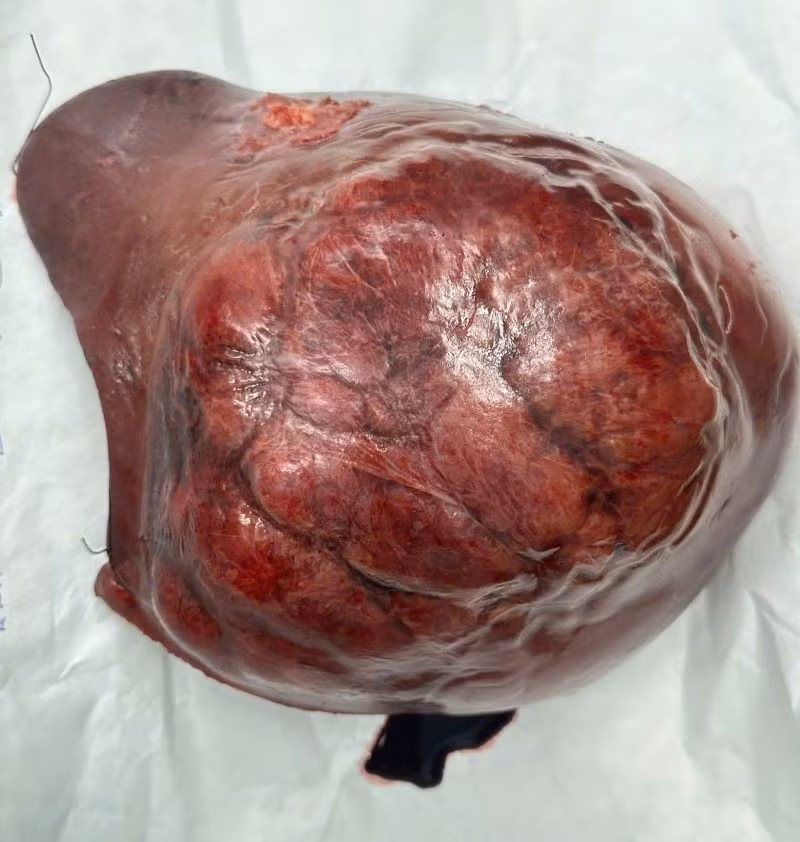

gan-2.jpg

Gan với khối u gan phải khổng lồ và sau khi cắt bỏ gan phải - Ảnh BVCC

Ở giai đoạn hai, ê kíp phẫu thuật đã thực hiện cắt bỏ toàn bộ gan phải mang khối u, với khối lượng hơn 1,5 kg. Ca mổ thành công, bệnh nhân hồi phục tốt và không gặp biến chứng suy gan do thiếu hụt thể tích gan chức năng.